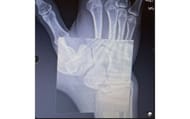

Dream also shared a picture of an X-ray of his wrist:

"Just had surgery on my wrist, so I can’t play Minecraft for a while. I pre recorded some awesome videos for you guys though! Thanks for all your support. Fingers crossed for a full recovery. I broke my wrist helping Sapnap train for his boxing match he was doing, and the bone never healed. Had to have a bone graft and a screw through the bone. When I’m back and recovered, 6 hunters won’t stand a chance!"